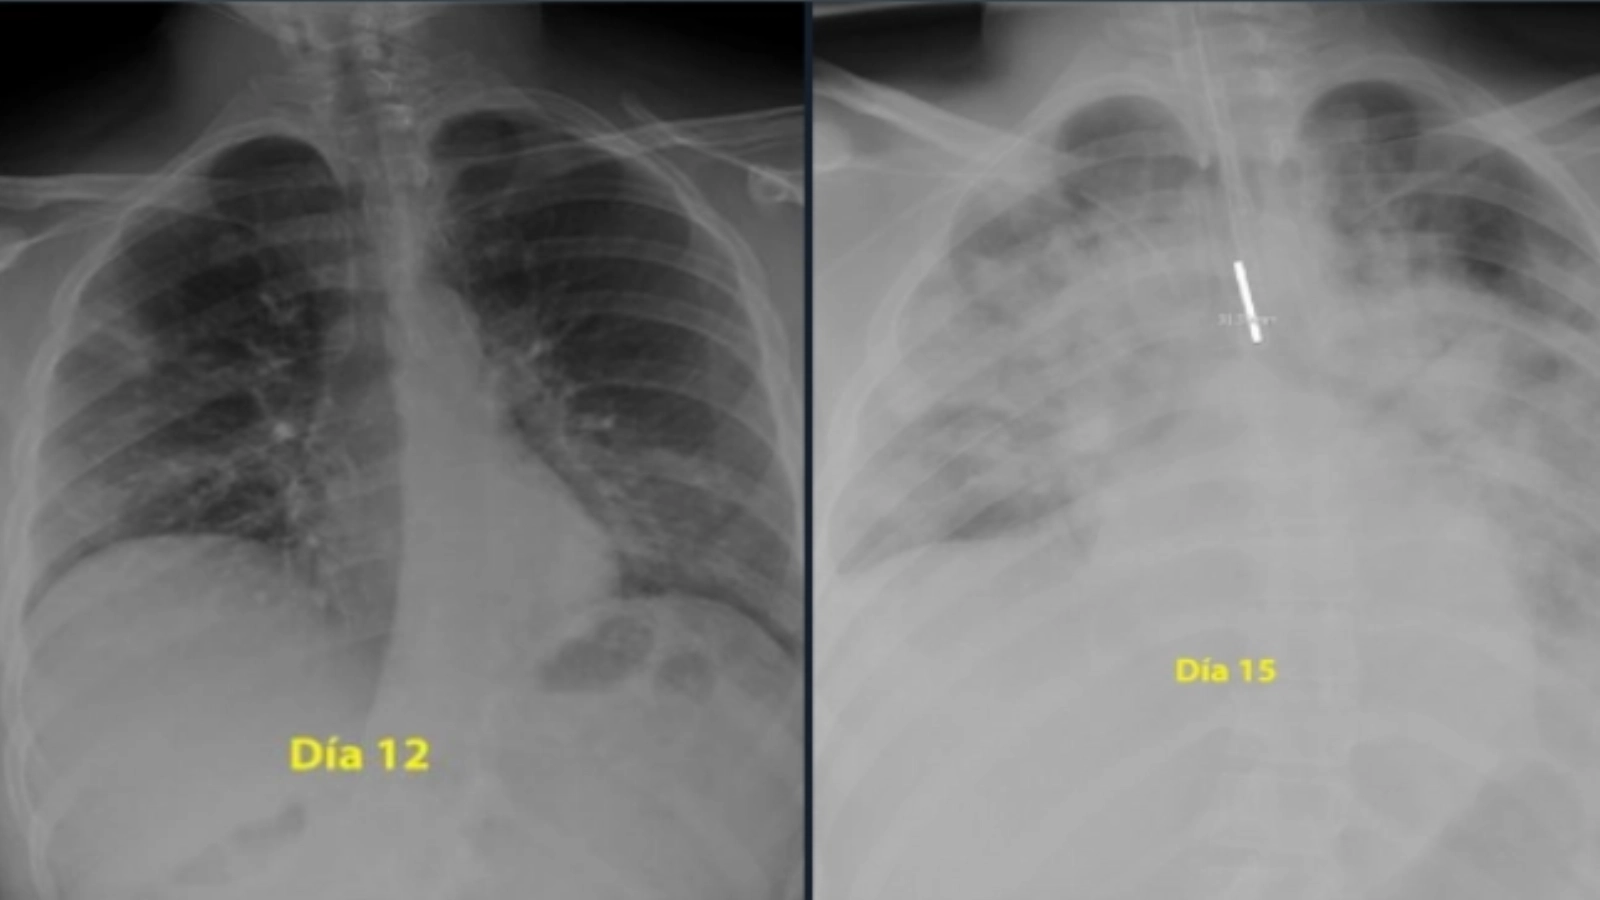

Potrivit adevarul.ro, un medic pneumolog din Spania a postat pe Twitter două radiografii care arată cum s-au degradat, în doar trei zile, plămânii unui tânăr de 28 de ani care a făcut o formă gravă de COVID-19. Momentan, noul coronavirus îi afectează, în general, mai puţin pe tineri, dar aceştia nu sunt totuşi, invincibili. Cercetătorii avertizeză că virusul suferă încă mutaţii.

„Pentru cei care cred că sunt nemuritori şi continuă să iasă în parc fără să acorde atenţie ordinului de a rămâne acasă, radiografiile unui băiat de 28 de ani intubat la Terapie Intensivă în spitalul meu, pentru coronavirus, arată gravitatea bolii”, a spus medicul, postând şi două fotografii cu plămânii tânărului, care, în doar trei zile de boală, au fost „măcinaţi” de pneumonie. „Plămânii sunt negri, albul este pneumonie”, a scris medicul pe Twitter.